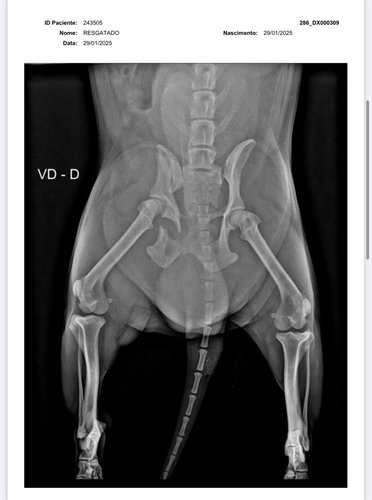

olá, eu sou a Samira, ajudo em uma ong de animais em Vilhena-RO e também resgato animais por conta própria. Encontrei esse pequeno cachorrinho abandonado a dias na chuva, sentindo tanta dor a ponto de não aceitar um sachê de comida. Levei ao veterinário e após buscar vários orçamentos, cheguei ao valor da vakinha, juntamente com a clínica Veterinária SOS animal, para a cirurgia do pequeno guerreiro. Não possuo condições de arcar com 100% da cirurgia, portanto, peço encarecidamente a ajuda de vocês para me ajudar e salvar a vida desse pequeno guerreiro. * Deixo abaixo o orçamento e os exames !